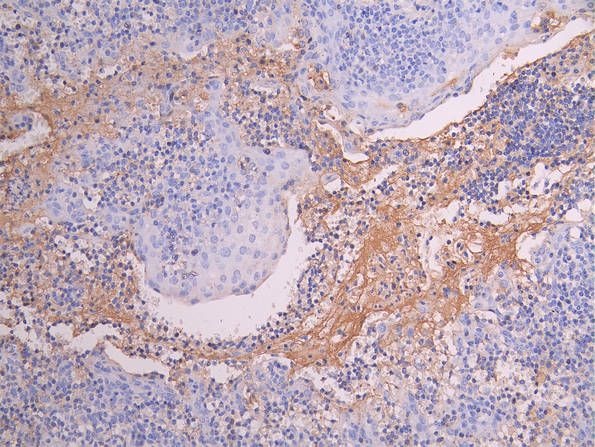

IHC image of CSB-RA014679MA1HU diluted at 1:150 and staining in paraffin-embedded human tonsil tissue performed on a Leica BondTM system. After dewaxing and hydration, antigen retrieval was mediated by high pressure in a citrate buffer (pH 6.0). Section was blocked with 10% normal goat serum 30min at RT. Then primary antibody (1% BSA) was incubated at 4°C overnight. The primary is detected by a Goat anti-human polymer IgG labeled by HRP and visualized using 0.05% DAB.